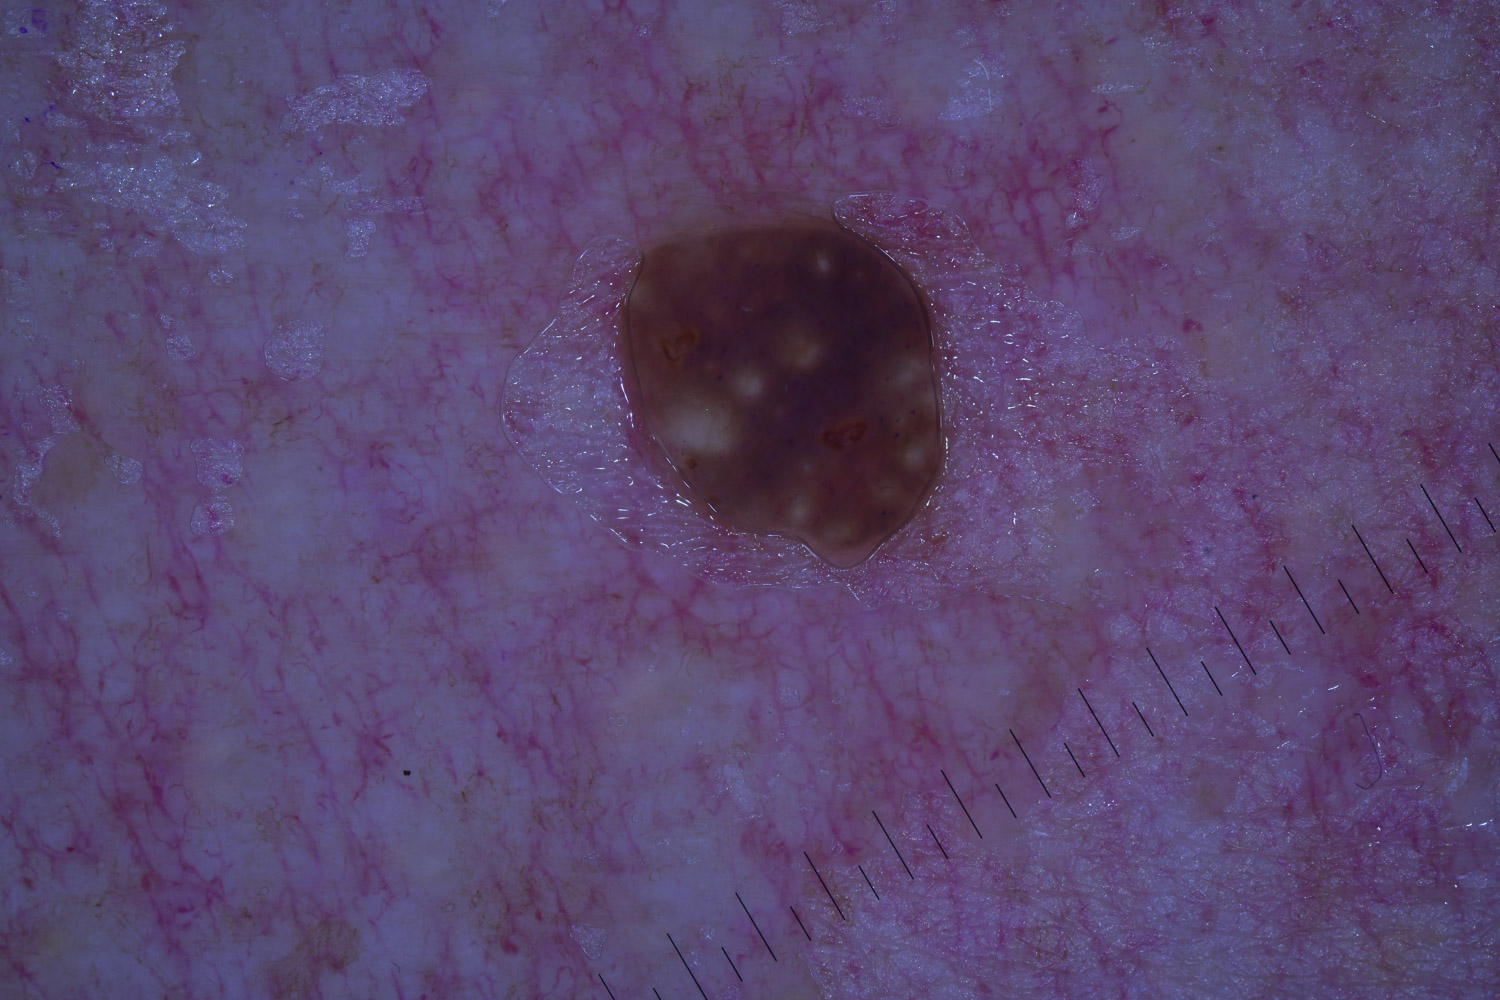

Case: 19